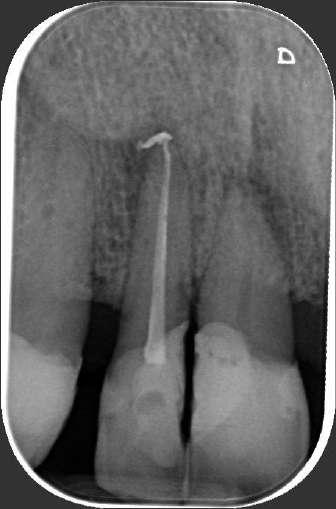

Effetto battericida di diversi sistemi Laser negli strati profondi della dentina

Nel corso degli anni molteplici sistemi laser hanno acquisito sempre più importanza in Endodonzia laser assistita; tra questi ricordiamo il laser Nd:YAG, il diodo, l’Er:YAG ed il laser Er,Cr:YSGG. Come ben sappiamo, lo scopo fondamentale della terapia endodontica è la disinfezione del sistema dei canali radicolari e della sua rete tridimensionale. Una volta attivata l’infezione dei tessuti pulpari, i batteri penetrano anche negli strati più profondi della dentina radicolare e propagano un’infiammazione periapicale con conseguente distruzione dei tessuti adiacenti. [1]

L’eradicazione dei batteri persistenti in aree distanti dal sistema tubulare rappresenta una sfida importante ed è cruciale per la conservazione a lungo termine del dente trattato endodonticamente.

Mano mano che l’infezione del sistema canalare si attua, il microambiente favorisce la selezione di alcuni ceppi batterici in grado di sopravvivere e proliferare. Le soluzioni irriganti impiegate agiscono attraverso il contatto diretto con i batteri

ma, a causa della insuLiciente profondità di penetrazione, i microrganismi presenti negli strati più profondi

della dentina non possono essere colpiti [2, 3]; inoltre è noto come batteri quali E. faecalis si formano da biofilm intra ed extra-radicolari, il che li rende ancor più diLicili da controllare [4-6].

Queste situazioni sono spesso responsabili di quei casi di resistenza alle terapie fin dall’inizio o che finiscono con fallimenti a lungo termine dopo trattamento endodontico.

L’introduzione della tecnologia laser in endodonzia ha migliorato notevolmente l’eLicacia e la percentuale di successo dei trattamenti canalari.

In generale i laser dentali, grazie alla loro miglior penetrazione nei tessuti, forniscono una maggiore accessibilità a zone

altrimenti irraggiungibili o scarsamente raggiungibili dagli irriganti [7-9].

La ricerca scientifica è stata inizialmente condotta con il Nd:YAG [10-13] e i laser a diodo [14-17], che hanno ottenuto un ampio consenso nel campo dell’endodonzia laser assistita; inoltre, per entrambe le lunghezze d’onda, è stata segnalata un’elevata capacità disinfettante.

Schoop et al hanno ottenuto 360 fette di dentina radicolare con uno spessore di 1 mm mediante taglio longitudinale di premolari appena estratti; i campioni sono stati sterilizzati a vapore e, successivamente, inoculati con una sospensione di E.Coli o E.faecalis.

potenza; utilizzando energie maggiori di 1.5W sono state nuovamente osservate riduzioni significative di E.coli con tutti i sistemi laser adottati, dove solo il diodo e il laser Er:YAG sono stati in grado di eliminare completamente E. faecalis. Durante l’esecuzione delle prove non è stata riscontrata alcuna relazione significativa tra l’aumento della temperatura e l’eLetto battericida.

Dopo l’incubazione, i campioni sono stati assegnati in modo casuale ai quattro diversi sistemi laser presi in esame; i campioni dentinali sottoposti a irradiazione laser “indiretta” attraverso la dentina dal lato privo di batteri sono stati poi sottoposti ad una classica valutazione microbiologica quantitativa. La microbiologia ha indicato che tutti i sistemi laser erano in grado di ottenere riduzioni significative in entrambi i ceppi di prova.

Possiamo pertanto concludere sostenendo che tutte le lunghezze d’onda testate sono adatte alla disinfezione anche degli strati più profondi della dentina potendo, quindi, costituire preziosi strumenti a disposizione del clinico.